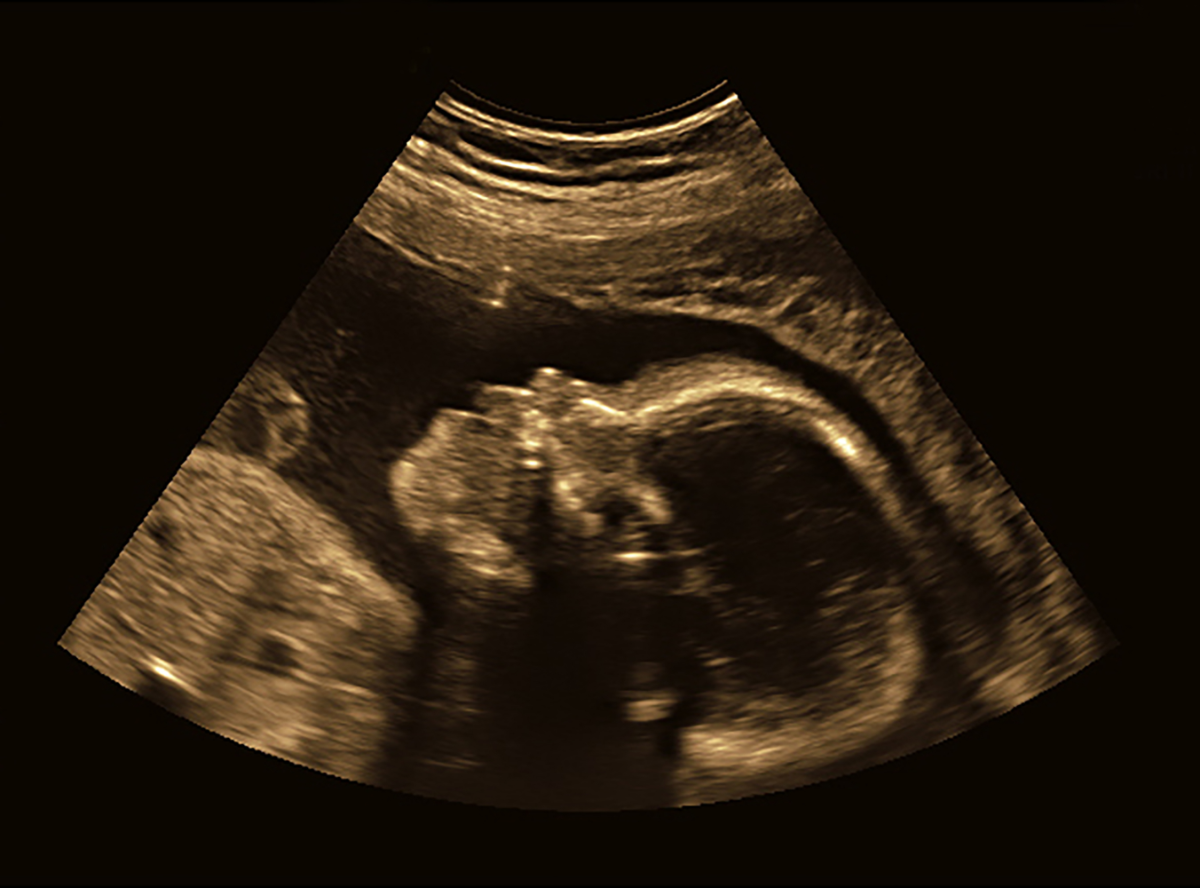

Zum ersten Mal den Herzschlag des ungeborenen Kindes auf dem Monitor sehen: ein besonders emotionaler Moment für werdende Eltern. Die Vorfreude auf das Baby ist riesig. Jetzt dreht sich alles um die Gesundheit und das Wohlbefinden von Mutter und Kind. Dazu tragen die Ultraschall-Untersuchungen beim Frauenarzt wesentlich bei. Was bei der Ultraschall-Untersuchung passiert und welche Screenings in der Schwangerschaft sinnvoll sind, lesen Sie in diesem Ratgeber.

Die Ultraschall-Untersuchung (med.: Sonografie oder Echografie, umgangssprachlich auch Ultraschall genannt) zählt zu den Standarduntersuchungen während einer Schwangerschaft. Dabei kontrolliert der Frauenarzt, wie sich das Kind entwickelt und ob die Schwangerschaft normal verläuft. Während einer Ultraschalluntersuchung, auch als Ultraschall-Screening bezeichnet, erhält der Arzt wichtige Informationen über die Gesundheit von Mutter und Baby. Diese sind für die weitere Vorsorge und die Vorbereitung auf die Geburt hilfreich.

Bei einer Ultraschall-Untersuchung sendet ein kleiner Schallkopf beziehungsweise eine -sonde Schallwellen in den Körper, die das menschliche Ohr nicht wahrnehmen kann. Treffen diese Wellen auf Gewebe im Körper, beispielsweise Organe oder Knochen, werden sie zurückgeworfen. Je nach Art des Gewebes ist das „Echo“ stärker oder schwächer ausgeprägt. Der Schallkopf nimmt die reflektierten Signale wieder auf und sendet sie an einen Computer. Dieser berechnet daraus ein bewegtes Bild, das auf einem Monitor zu sehen ist.

Alle weiteren Ultraschall-Untersuchungen während der Schwangerschaft erfolgen dann über die Bauchdecke (abdominaler Ultraschall). Dabei trägt der Arzt ein sogenanntes Kontaktgel auf den Bauch der Schwangeren auf. Dieses benötigt er, damit die Schallwellen über die Haut in den Körper gelangen. Dann bewegt er den Schallkopf über den Bauch der Schwangeren. Reflektieren der Körper des Kindes und der Mutter diese, erscheinen entsprechende Bilder auf einem Monitor. Laien erkennen darauf in der Regel nur schwer, welche Körperteile genau zu sehen sind. Deshalb erklärt der Gynäkologe den werdenden Eltern Schritt für Schritt, was er gerade untersucht und was auf dem Bildschirm abgebildet ist.